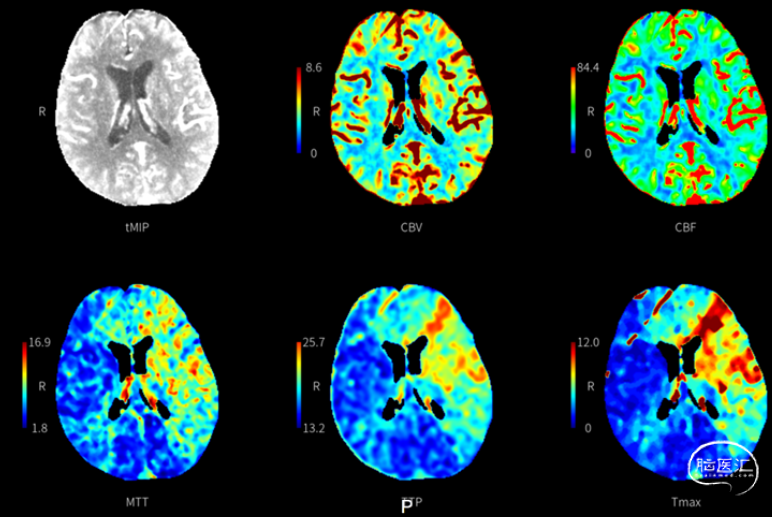

入院后急性行CT平扫+CTP,结果提示:颅内未见明显出血,左侧颈内动脉C7段闭塞。左侧大脑中动脉大片地灌注区,Core 0ml,Penumbra 194.9ml。溶栓前血液学检查及临床评估无溶栓禁忌。经家属签字同意于12:25予阿替普酶49.5mg(体重55kg)静脉溶栓治疗,DNT时间28min。

CTP: